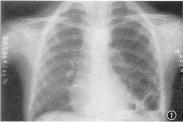

• 支氣管肺隔離癥

628健康網為您分享有關支氣管肺隔離癥的癥狀,支氣管肺隔離癥的治療方法,支氣管肺隔離癥的預防知識,支氣管肺隔離癥的癥狀...